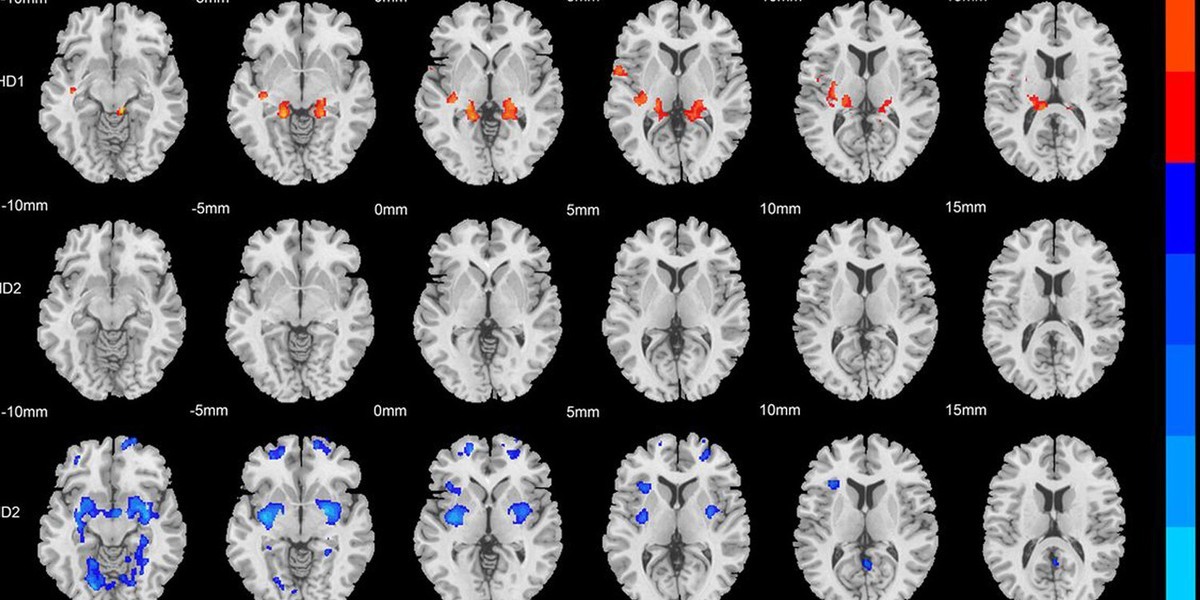

برای حل این مشکل، تیم از یه الگوریتم یادگیری ماشین پیشرفته استفاده کرد تا بیمارها رو صرفا بر اساس آناتومی مغشون گروه بندی کنه و بدین ترتیب تقسیم بندی جدید بیش فعالی را ممکن سازد. این ابزار محاسباتی حجم عظیمی از داده های آناتومیک رو بررسی می کنه تا الگوهای بیولوژیکی پنهانی رو پیدا کنه که ممکنه از چشم انسان دور بمونه. این الگوریتم با موفقیت دو زیرگروه فیزیکی مجزا رو در بین گروه بیمارها شناسایی کرد.

زیرگروه اول با افزایش ماده خاکستری در چندین ناحیه از مغز مشخص می شد. وقتی محقق ها دقیق تر بررسی کردن، متوجه شدن که این افزایش های فیزیکی بیشتر در نواحی پیشانی و مخچه متمرکز شده. نواحی پیشانی عملکردهای شناختی سطح بالا مثل حافظه کاری رو مدیریت می کنن، در حالی که مخچه مسئول توجه و هماهنگی حرکتیه.

زیرگروه دوم واقعیت فیزیکی تقریبا متضادی رو نشون داد. بیماران این گروه در مقایسه با گروه کنترل، کاهش گسترده یا تحلیل رفتن (آتروفی) ماده خاکستری رو نشون دادن. این از دست دادن بافت به خصوص در مخچه دوطرفه، نواحی پیشانی و هیپوکامپ مشهود بود.

برای زیرگروه اول، این تحلیل پیشرونده پیوندهای قوی ای رو بین گره های خاص مغزی و حوزه رفتاری بی توجهی نشون داد. داده ها نشون دادن که اختلال در توجه، نقص بیولوژیکی اصلی برای این کودکان محسوب میشه. نواحی پیشانی و مخچه به عنوان قطب های اصلی برای این تغییرات ساختاری زنجیره ای عمل کردن.

برای زیرگروه دوم، تحلیل شبکه علی الگوی خیلی گسترده تری از اتصالات ساختاری رو آشکار کرد. تغییرات جسمی در این کودکان توسط حوزه های رفتاری متعددی، از جمله بیش فعالی و تکانشگری شدید، هدایت می شد. این الگوی گسترده نشون دهنده شدت کلی بیشتر این وضعیت در گروه دومه، که در اون هیپوکامپ به عنوان یه قطب اصلی عمل می کنه.